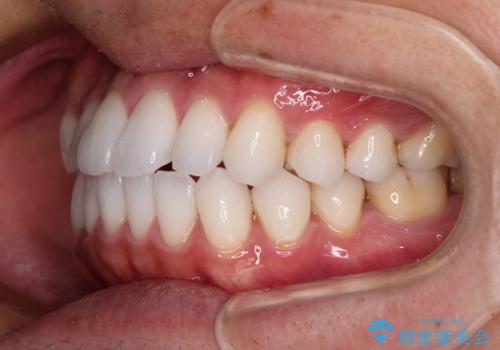

前歯のクロスバイトを改善 インビザラインによる矯正治療

今回は、ワイヤー装置を併用することなく治療を行い、トラブルなく、満足のいく歯列に整えることができました。

矯正治療の途中でホームホワイトニングを併用され、術前とは見違えるほどきれいな口元となりました。